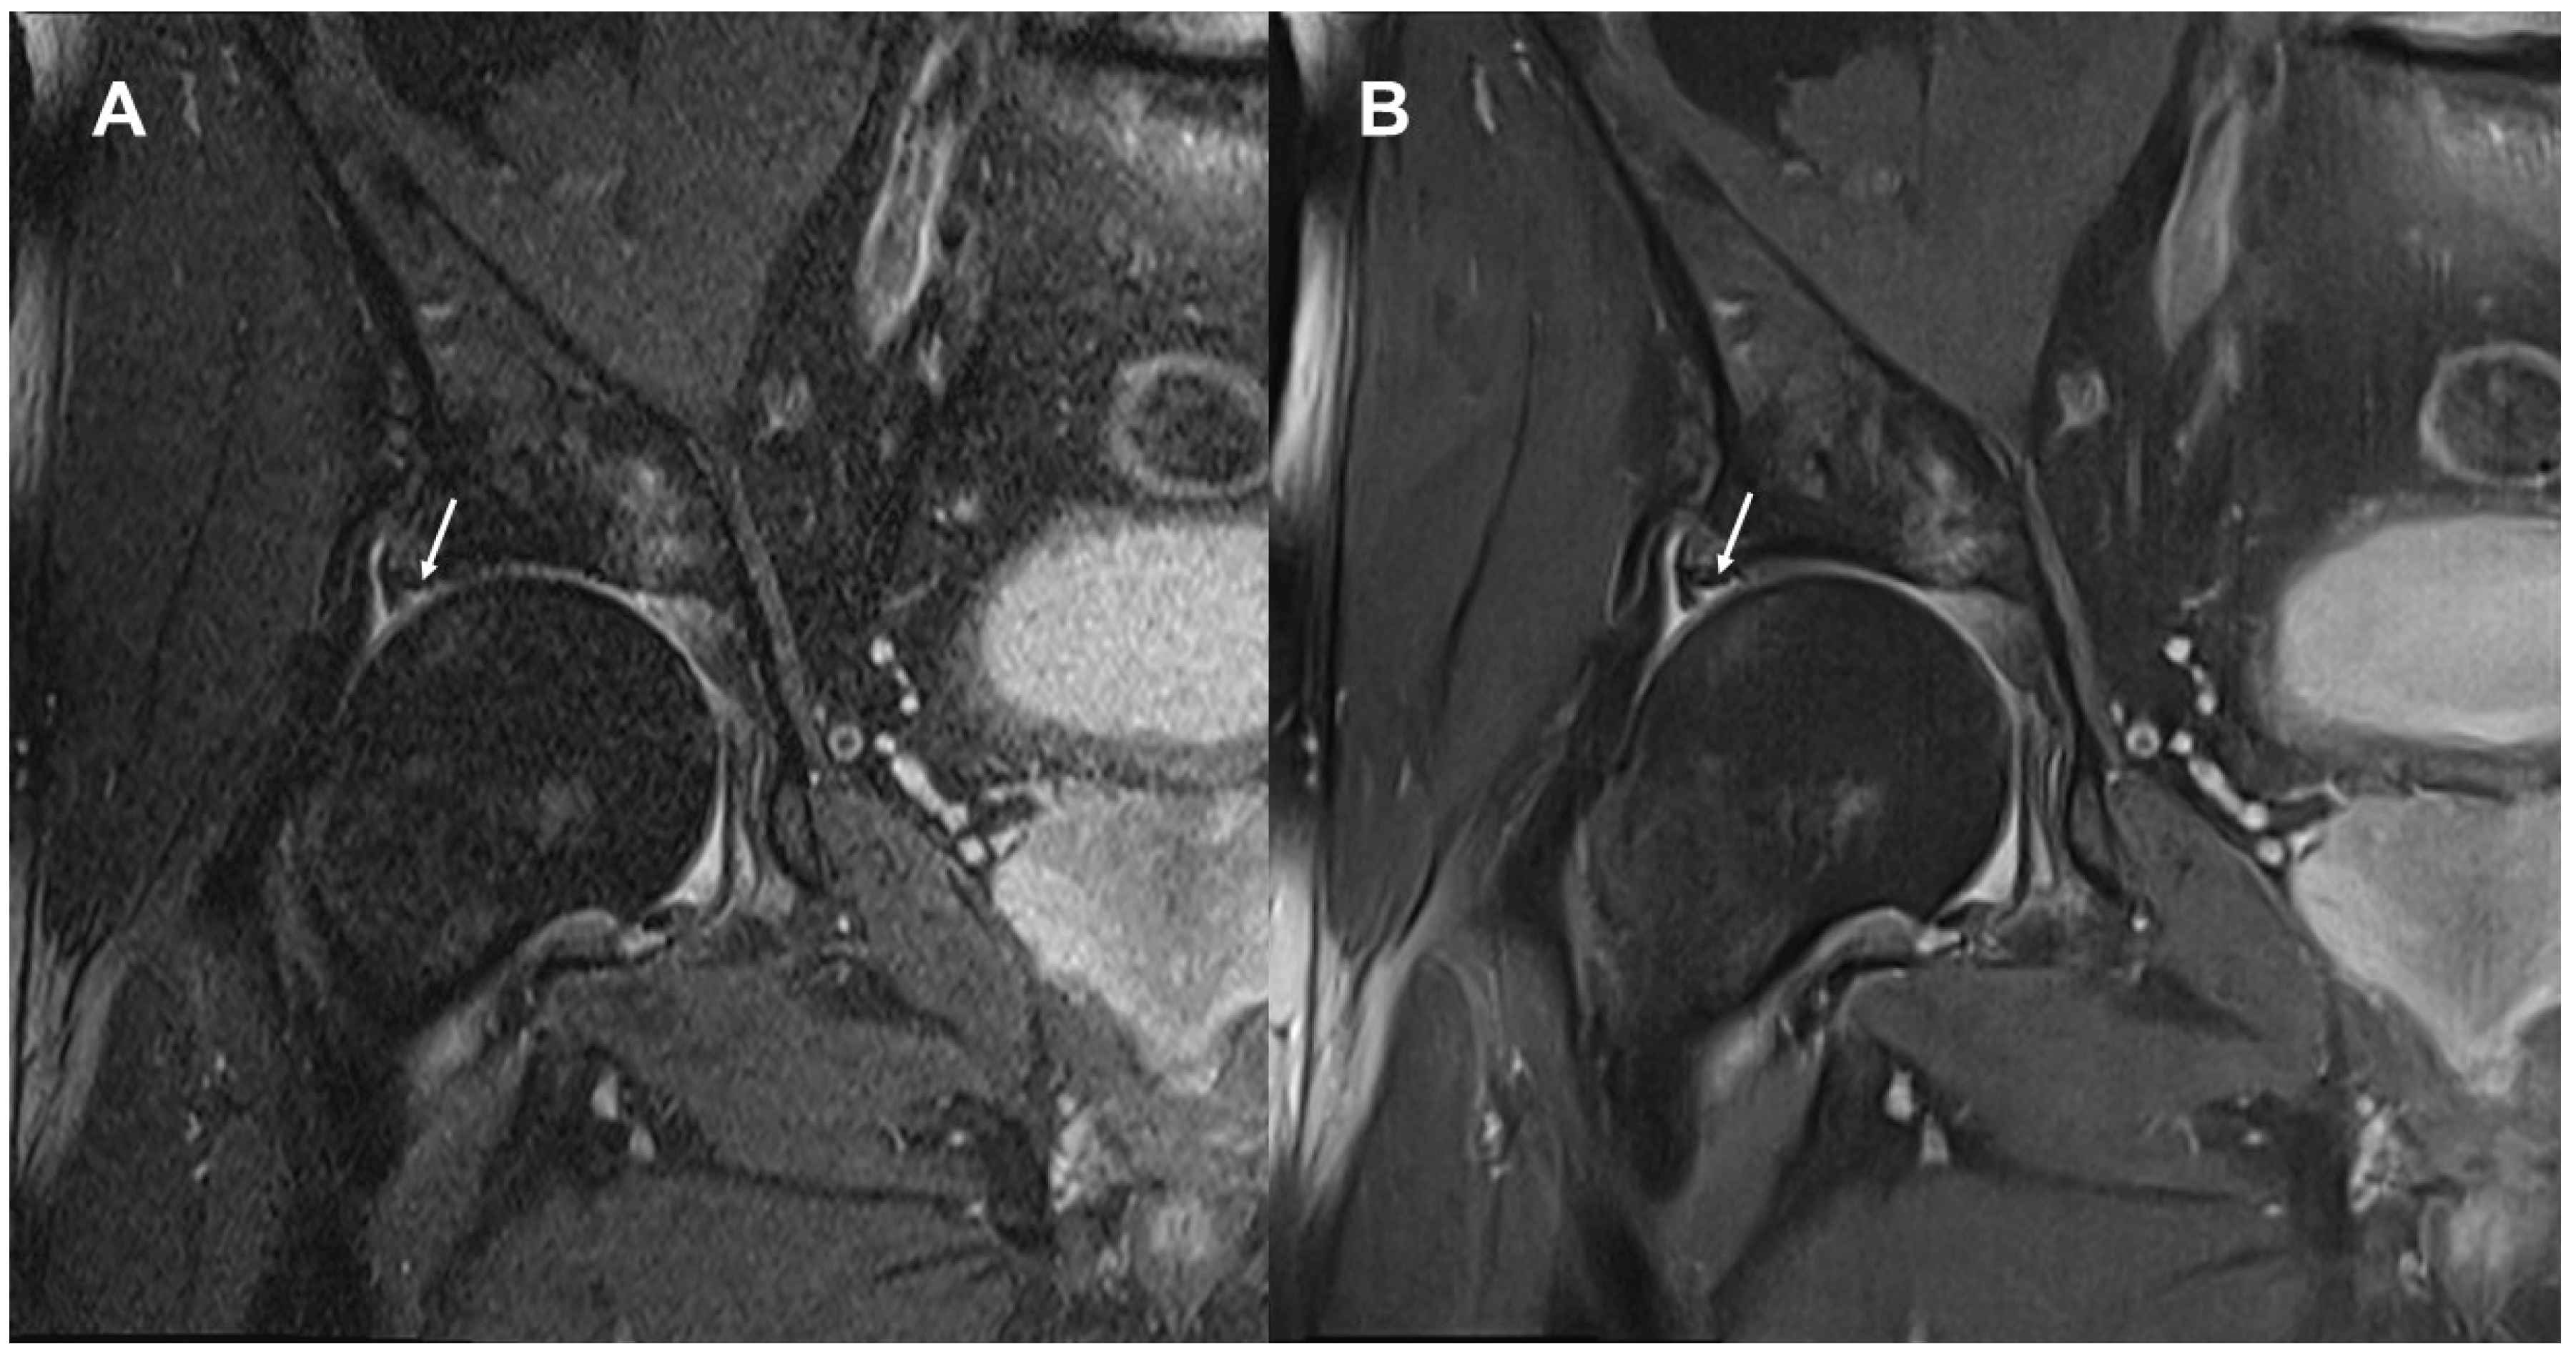

3.2. Delineation of Anatomic Structures and Internal Derangement